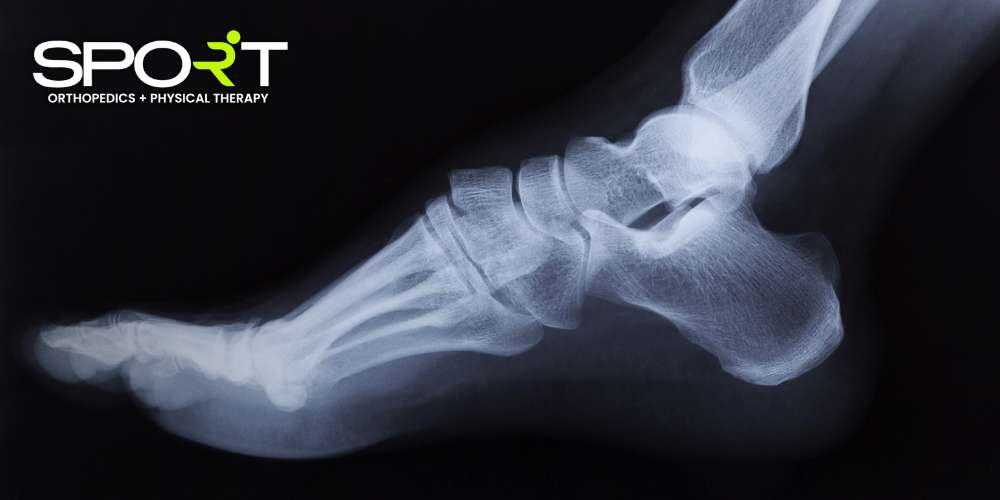

An ankle fracture occurs when one or more bones in the ankle joint are broken. This type of injury is often the result of a fall, a direct blow, or a severe twist of the ankle, and it can cause intense pain that makes it difficult to move or put weight on the injured foot.

Ankle fractures vary in severity, from minor cracks in the ankle bone to more complex breaks that require surgical intervention. If you suspect an ankle fracture, it’s important to seek medical attention promptly to prevent further complications and ensure proper healing.

In contrast, a fracture involves a break in one or more of the three bones that form the ankle joint. A fractured ankle typically causes more intense pain and significant swelling and may lead to visible deformity or an inability to move the ankle. While both injuries require medical attention, fractures generally need more intensive treatment, such as immobilization or surgery, to ensure proper healing.

In contrast, a fracture involves a break in one or more of the three bones in the ankle. A fractured ankle usually causes immense pain and significant swelling and often makes it impossible to put weight on the foot and ankle. While both ankle injuries can cause discomfort and limit mobility, an ankle fracture is generally more serious and requires a longer recovery period compared to an ankle sprained.